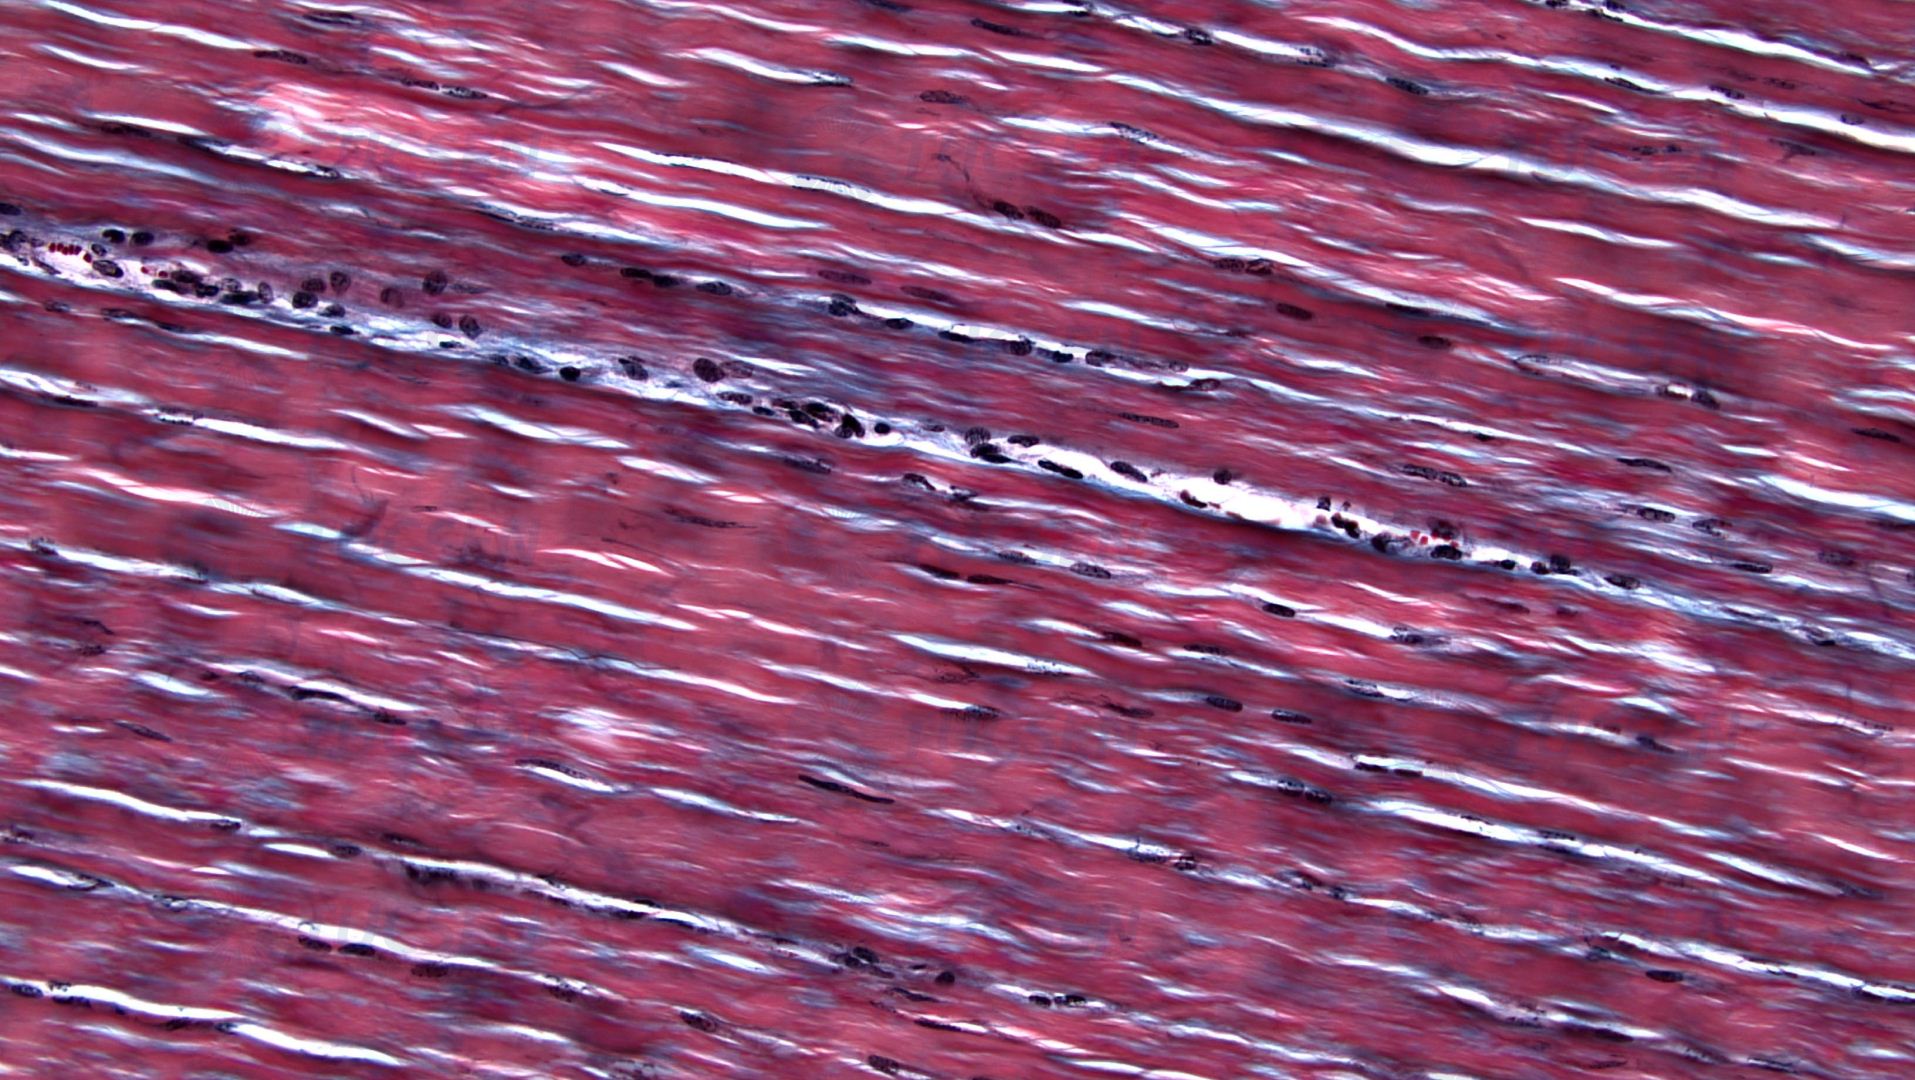

Elastic Fibers By TrueChrome II